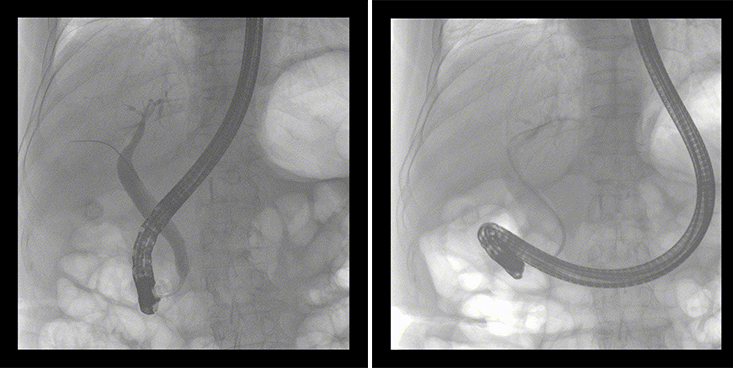

一位86歲的女性患者近來出現(xiàn)腹痛,入院后CT檢查并結(jié)合臨床表現(xiàn)被診斷為急性膽囊炎伴膽囊結(jié)石。經(jīng)專家團隊協(xié)商并與患者家屬溝通,決定對患者實施經(jīng)內(nèi)窺鏡逆行胰膽管造影(ERCP)。

ERCP(經(jīng)十二指腸鏡下逆行胰膽管造影)現(xiàn)已成為比較成熟的微創(chuàng)介入技術(shù),被廣泛的應(yīng)用于臨床,ERCP也是消化內(nèi)鏡領(lǐng)域難度大、風(fēng)險大、技術(shù)復(fù)雜的微創(chuàng)手術(shù),其并發(fā)癥多為致命性,ERCP手術(shù)對醫(yī)生的要求很高,因此,ERCP醫(yī)生又被稱為“刀尖上的舞者”。因為手術(shù)難度較大,過程復(fù)雜,需要C形臂精準(zhǔn)的配合,對影像清晰度的要求也非常高。

普愛醫(yī)療移動式平板中C為本次ERCP手術(shù)提供實時無損高清影像,幫助醫(yī)生精準(zhǔn)定位。“成像效果非常棒!完全不輸國際大牌的醫(yī)學(xué)影像設(shè)備……”鼓樓醫(yī)院江北國際醫(yī)院內(nèi)鏡中心手術(shù)團隊對普愛醫(yī)療移動式平板中C的成像效果給與了高度的評價。

在消化內(nèi)科主任的領(lǐng)導(dǎo)和多科室全力配合下,南京鼓樓醫(yī)院江北國際醫(yī)院成功完成了首例ERCP手術(shù)。